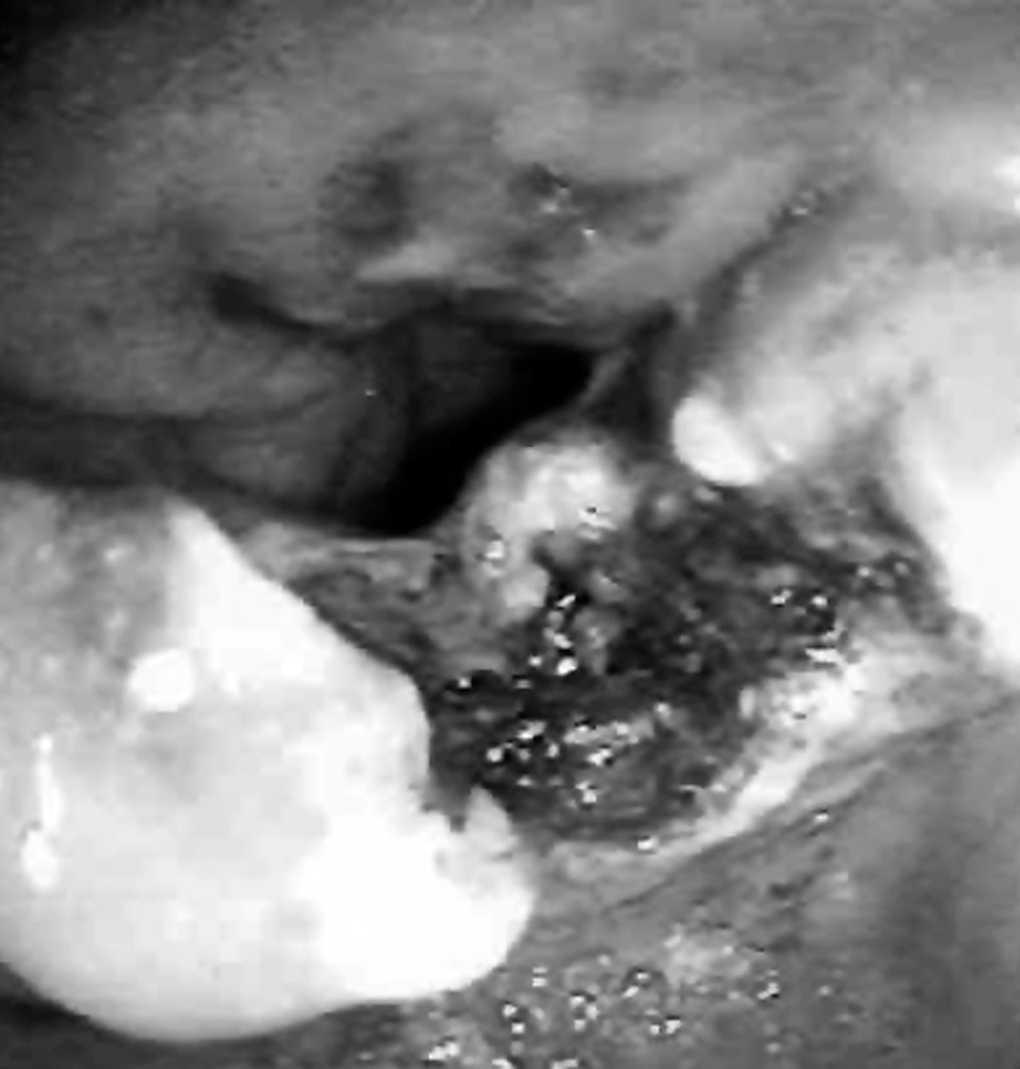

La técnica endoscópica consiste en la incisión diatérmica del músculo cricofaríngeo causante del área de alta presión que dificulta o impide el paso del bolo alimentario desde el divertículo al esófago. El procedimiento se realiza en la sala de endoscopia, bajo anestesia tópica faríngea y sedación por vía intravenosa (sin anestesista presente) y con profilaxis antibiótica con amoxicilina-ácido clavulánico. Inicialmente se extrae todo el material alimentario retenido en el divertículo y se explora meticulosamente la mucosa para descartar áreas sospechosas de transformación neoplásica. Posteriormente se intuba el esófago y se introducen 2 guías de 0,035 pulgadas sobre las que se implantan 2 sondas orogástricas CH12. A continuación se reintroduce un gastroscopio terapéutico Pentax EG3440 con canal de trabajo de 3,5 mm y se procede a realizar la cricofaringomiotomía con un esfinterotomo de aguja de dos luces Wiltek PK20320 montado sobre una guía Boston Scientific AmplatzTM Super Stiff que permite transmitir la torsión para orientar anteriormente la punta angulada entre 60° y 90° (fig. 1). La corriente diatérmica monopolar se obtiene de un generador ERBE 200 ICC ajustado a 80W y con el modo "endocut" activado. La incisión se extiende caudalmente siguiendo el valle central dejado por la impronta de las 2 sondas orogástricas sobre el tabique que separa el divertículo de la luz esofágica (fig. 2). La incisión se amplía más allá de las fibras musculares circulares del músculo cricofaríngeo hasta una distancia de unos 5 a 10 mm del fondo del divertículo. El lecho cruento se coagula con plasma de Argón (ERBE APC 300) para prevenir una hemorragia tardía. Las sondas orogástricas se retiran al terminar el procedimiento (fig. 3). La tolerancia líquida se inicia a las 12 h y la sólida a las 36 h.

Fig. 1. Paciente 1. Situación inicial. Se observan las dos sondas introducidas en la luz esofágica (superior) y el esfinterotomo de aguja con la punta angulada y apoyada sobre el tabique cricofaríngeo. La luz inferior corresponde al divertículo.